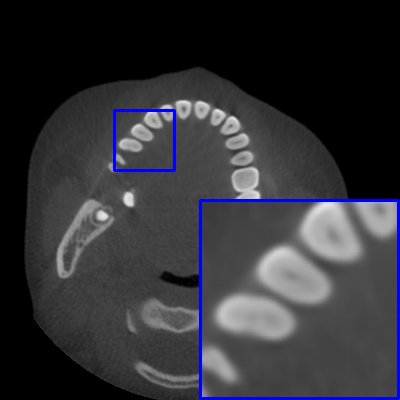

Figure 3: Visual comparison of MAR images by different methods on synthetic MA image. The PSNR (dB)/SSIM results are reported below each image for reference.

Results on synthetic MAR. In Table 1, we provide the quantitative results. One can see that our MARformer-L outperforms the other methods in terms of PSNR and SSIM, but needs only 11.76M parameters and 60.25G FLOPs. Note that the second best method Uformer-B has 50.42M parameters and 205.82G FLOPs. Besides, our MARformer-T achieves similar PSNR and SSIM results with Uformer-T, but needs only 0.40M parameters and 12.82G FLOPs compared to 5.24M and 25.39G for Uformer-T. Our MARformers also achieves faster inference speeds than the Uformers, though with inferior Dice scores, respectively. The qualitative results of visual quality are presented in Fig. 3. We observe that our MARformer-L well recovers the teeth shapes and obtains higher PSNR and SSIM results than the other comparison methods. The light-weight MARformer-L achieves similar results to Uformer-T. All these results validate that our MARformer is more efficient than the comparison methods on dental CBCT MAR.